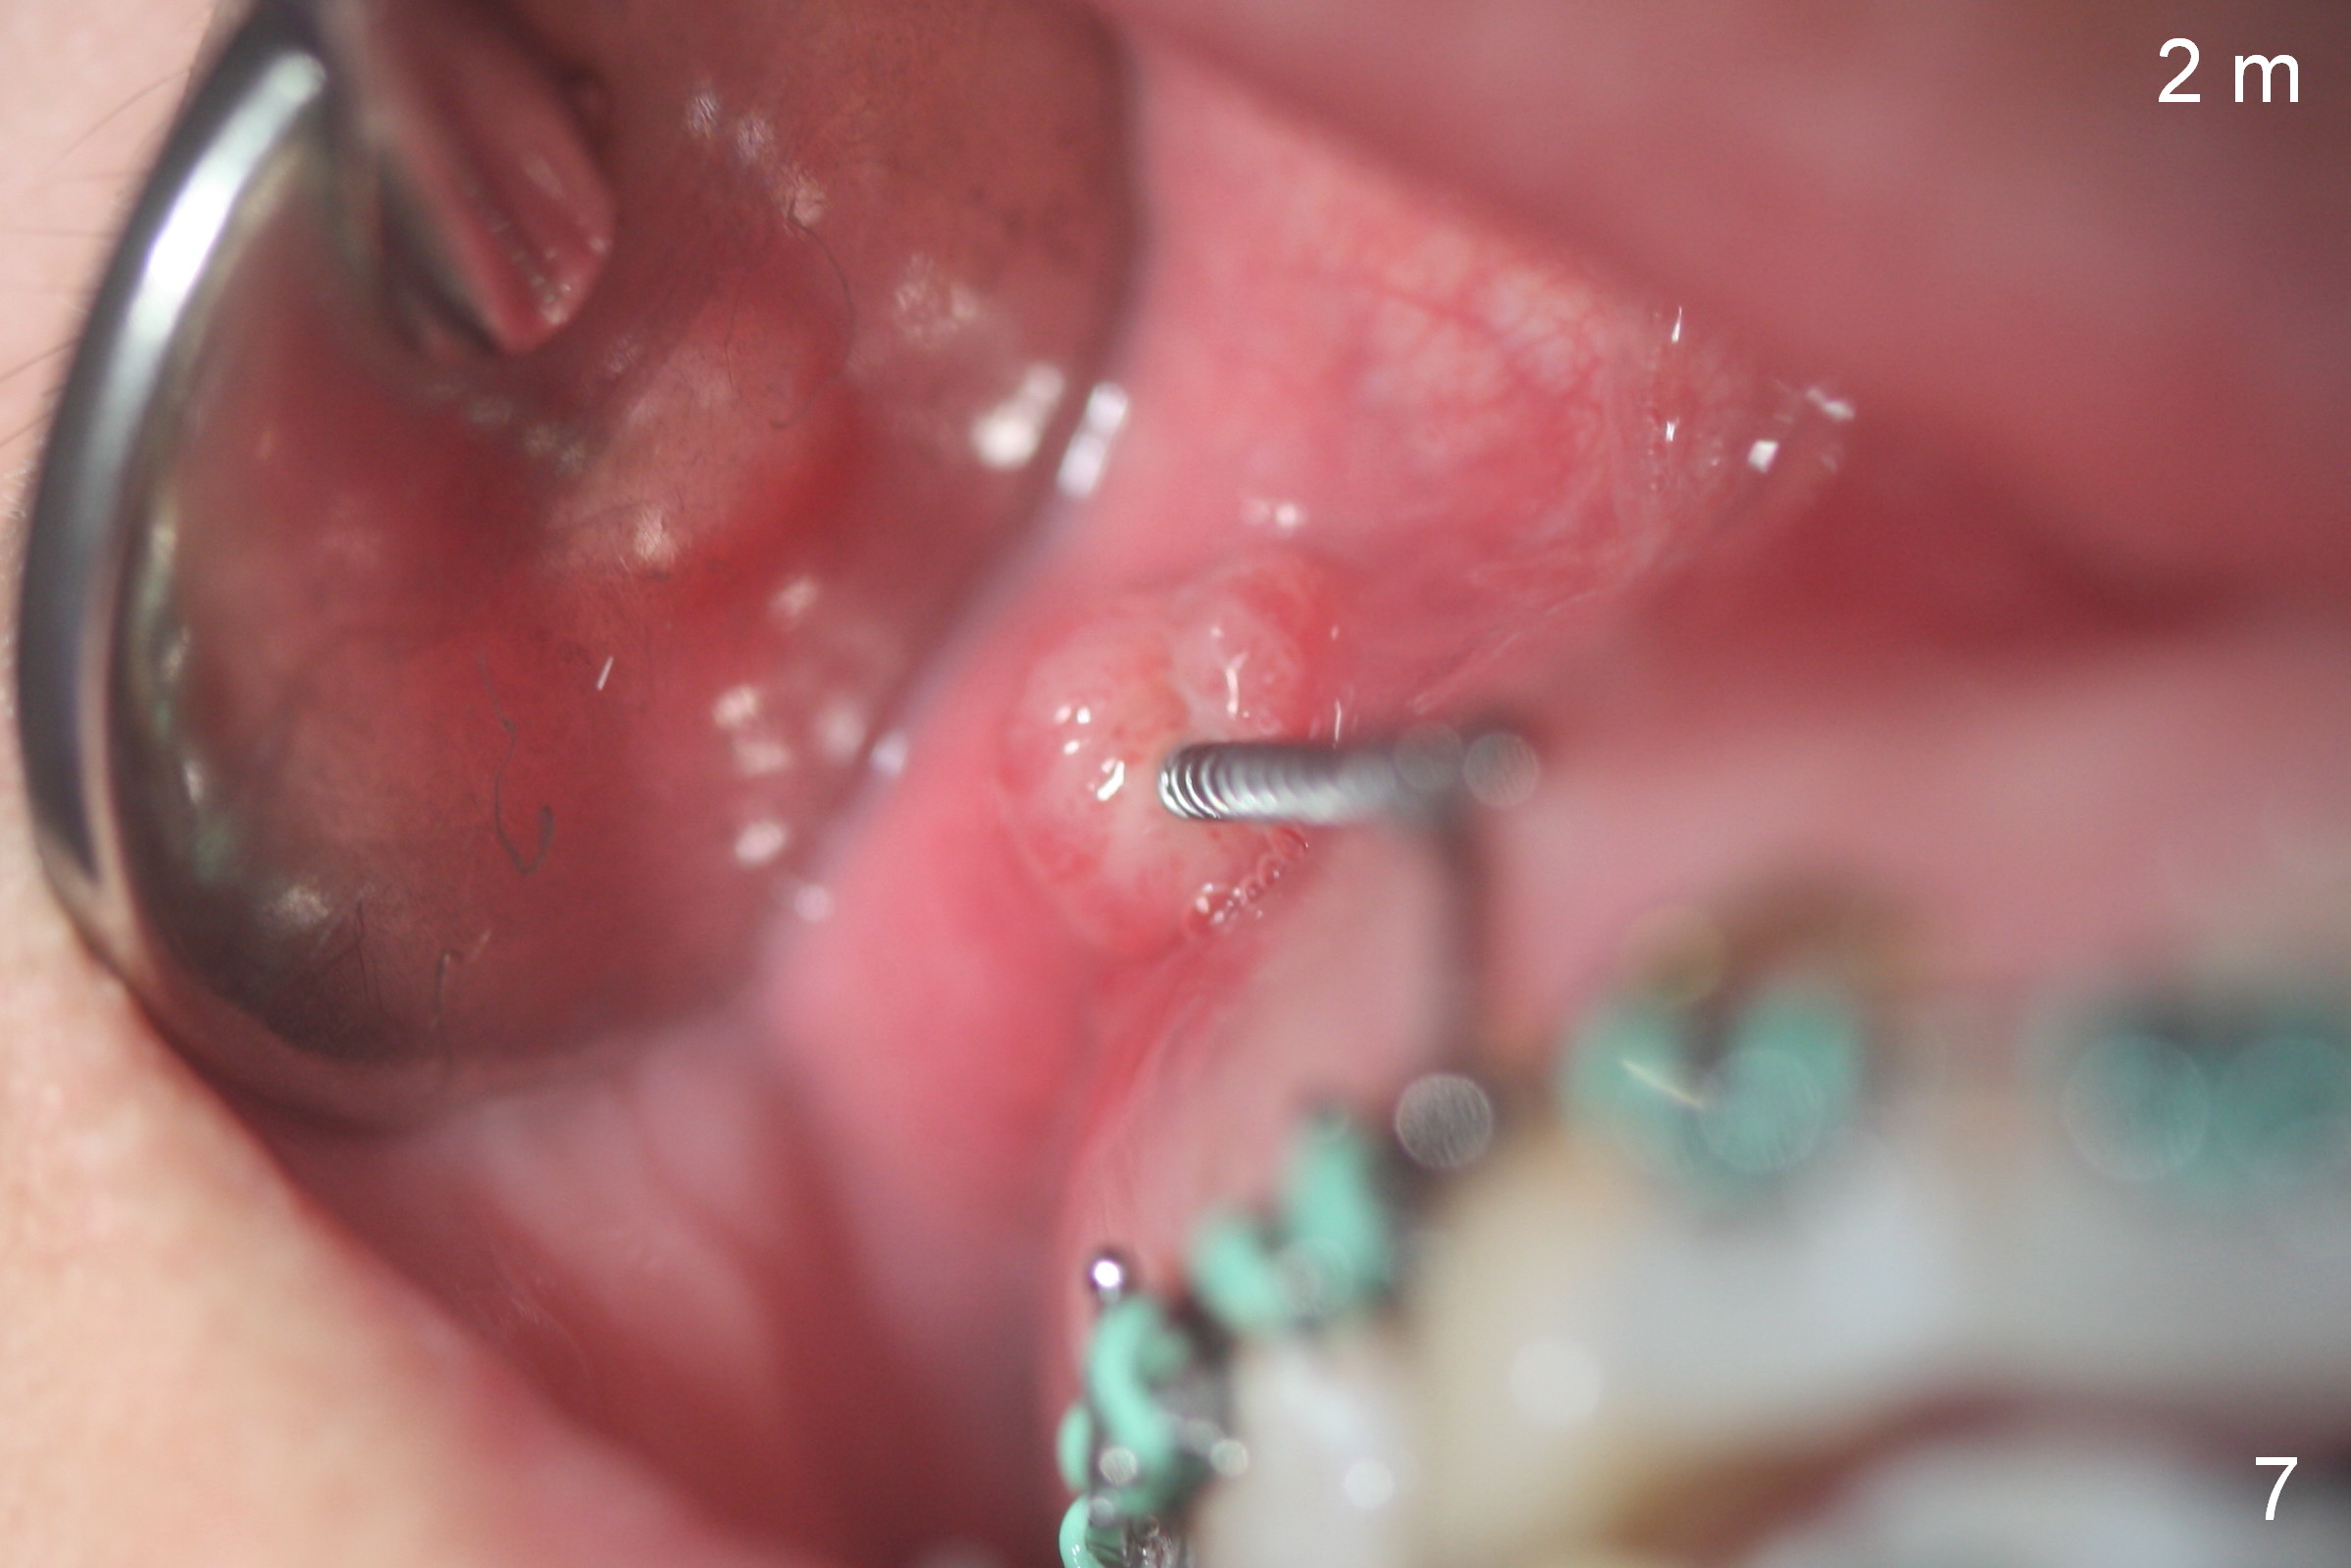

Postop follow up at 1 week (Fig.5,6), 2 months (Fig.7,8) and 3 months (Fig.9,10).  Granulation tissue forms around the entrance of closed coil spring with tenderness 2 months postop (Fig.7,8).  Pain persists especially on the left.  Tension of coiled spring associated with zygomatic implants is low; new coiled springs are added for the posterior implants (Fig.9,10).  Later the left spring associated with the left zygomatic implant fractures.